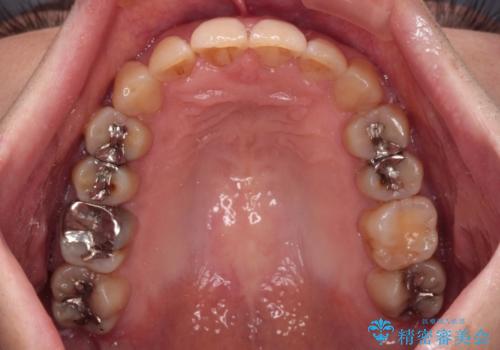

ディープバイトと前歯のデコボコ インビザラインによる矯正治療

- 前歯のディープバイトと叢生を気にして来院された患者様です。

目立ちにくい装置を希望されていたため、ワイヤー装置とインビザラインを提案したところ、インビザラインを希望されました。

下顎大臼歯が手前に倒れていたため、起き上がらせることで咬み合わせ高さを挙上し、ディープバイトと叢生を改善することとしました。